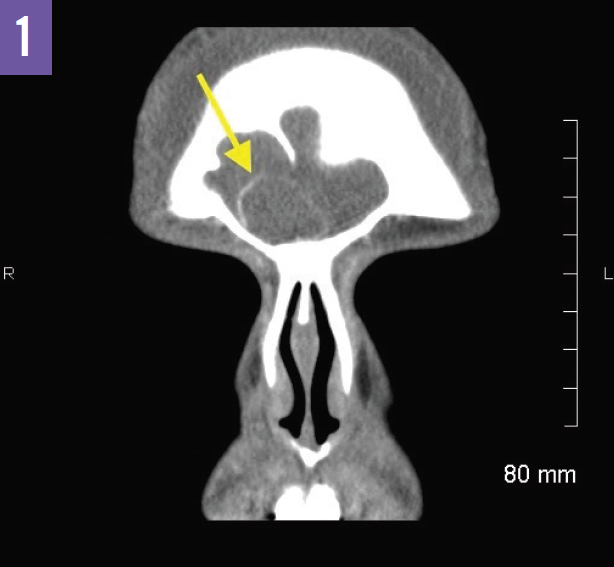

From radiopaedia.org

Pott puffy tumor Image Pott's Puffy Tumor Icd 10 It is characterized by a. pott’s puffy tumor (ppt) describes forehead swelling with associated frontal bone osteomyelitis and a. pott puffy tumor is a subperiosteal abscess due to associated frontal skull. citation, doi, disclosures and article data. pott’s puffy tumor describes an infection of your frontal bone (forehead) along with an abscess that develops in the.. Pott's Puffy Tumor Icd 10.